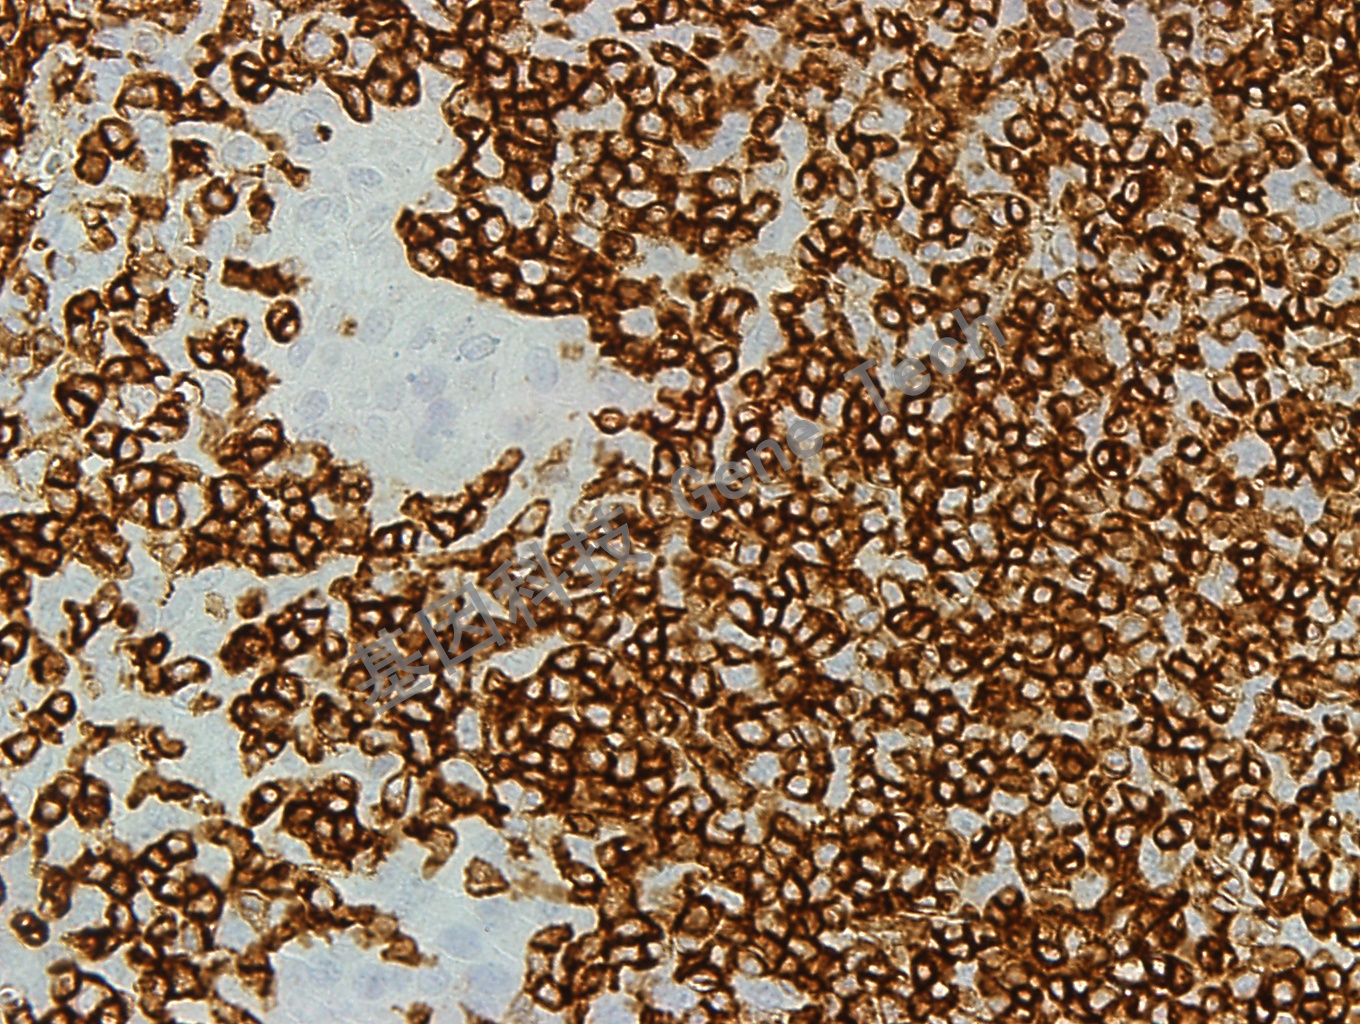

| 克隆號:PD7/26 | 陽性對照:扁桃體 | 陽性部位:細(xì)胞膜 |

| 簡介:人淋巴細(xì)胞表面的CD45 分子因其剪切形式不同有5 中蛋白形式依次為:CD45RO、RB、RA、RBC 和RABC,其分子量(不計(jì)糖鏈)分別是180、190、195、205 和220kDa。其中CD45RB 表達(dá)在B 細(xì)胞、某些T 細(xì)胞亞群、單核細(xì)胞、巨噬細(xì)胞中,粒細(xì)胞中表達(dá)較弱。CD45 抗體PD7/26 克隆是出現(xiàn)于上世紀(jì)80 年代初經(jīng)典克隆, 能夠與5 種CD45 蛋白的3 種類型 (分子量為 190,205 和220 kDa)結(jié)合。其提示意義基本同CD45,但在Langerhan’s 細(xì)胞與小部分T 細(xì)胞中不表達(dá)。 | ||

| 扁桃體石蠟切片,用 CD45RB(GT2219)染色,細(xì)胞膜陽性,DAB 顯色。(40X) | ||